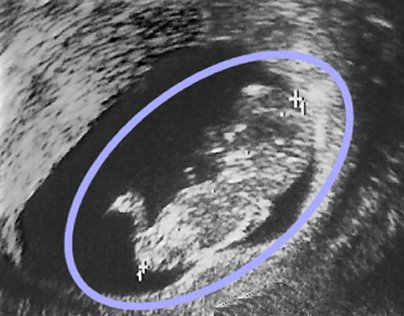

Muestra de sonograma

Este sonograma ha sido tomado en el tercer mes de embarazo, muestra un feto masculino (cabeza, cuerpo y piernas son claramente reconocibles dentro del óvalo azul)